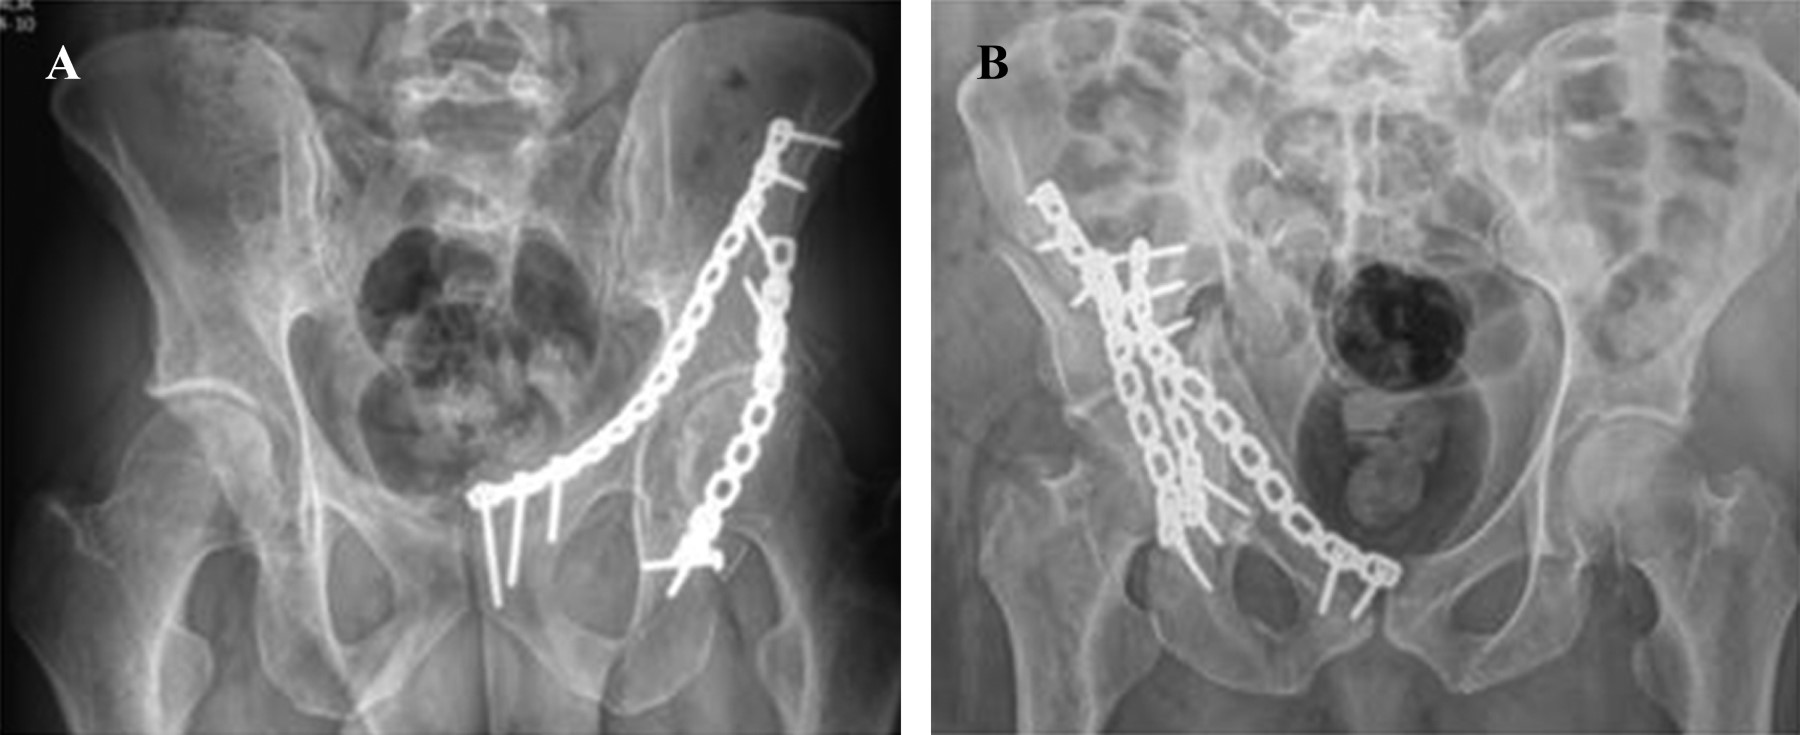

Para la obtención de los datos se revisó parte de la información en el expediente clínico como la edad, sexo, mecanismo de lesión, tiempo entre la lesión y el procedimiento quirúrgico, sangrado transquirúrgico, tiempo quirúrgico, complicaciones tempranas y lesiones asociadas. Para la evaluación radiográfica se aplicaron los criterios de reducción radiográfica de Matta a las radiografías postquirúrgicas inmediatas de los pacientes en proyecciones anteroposterior, alar y obturatriz, que se encontraban en el sistema del hospital llamado infosalud, siendo anatómica (menor de 1 mm), casi anatómica (1-3 mm) e imperfectas (mayor de 3 mm)9 (Figura 1).

Los pacientes fueron evaluados con radiografías anteroposterior, alar y obturatriz posterior al procedimiento quirúrgico aplicando los criterios de Matta, con resultados radiográficos anatómicos (menor de 1 mm) 21 pacientes (67.7%), casi anatómicos (1-3 mm) siete (22.5%) e imperfectos (mayor de 1 mm) tres (9.6%) pacientes. Los resultados funcionales fueron evaluados por lo menos pasados 12 meses del procedimiento quirúrgico (12-59) por el investigador principal mediante interrogatorio y observación, aplicando la escala de Merle d'Aubigné y Postel, dando como resultado ocho (25.8%) con resultados excelentes, 16 (51.6%) con resultado bueno, moderado cinco (22.5%) y malo dos (16.1%) (Tabla 2).

Figura 1